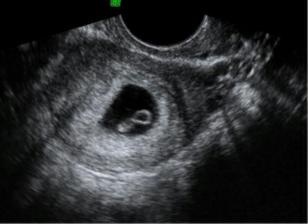

Zaciatok

Pre nase srdiecko o ktore sme prisli 1.1.2010 v 14. tyzdni...